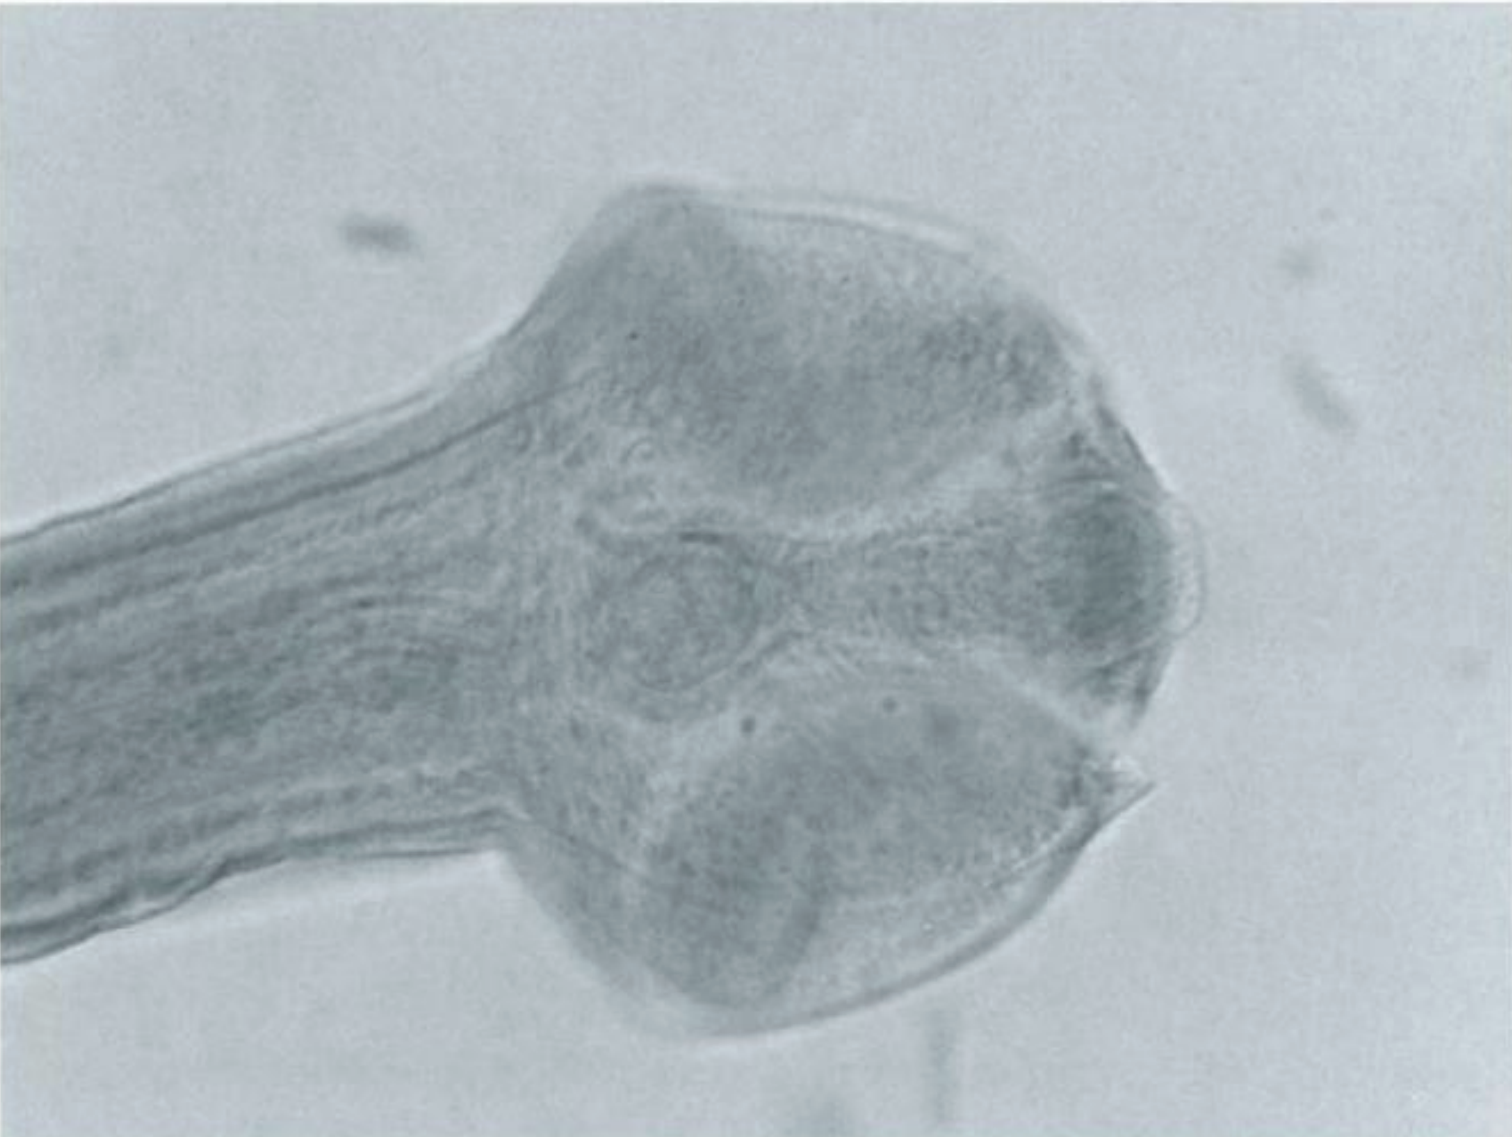

name the shape of its scolex?

Bothriate